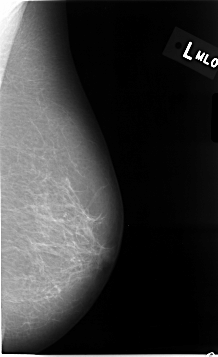

ics_version 1.0 filename C-0014-1 DATE_OF_STUDY 22 6 1992 PATIENT_AGE 83 FILM FILM_TYPE REGULAR DENSITY 1 DATE_DIGITIZED 11 9 1997 DIGITIZER LUMISYS LASER SEQUENCE LEFT_CC LINES 4648 PIXELS_PER_LINE 2696 BITS_PER_PIXEL 12 RESOLUTION 50 NON_OVERLAY LEFT_MLO LINES 4632 PIXELS_PER_LINE 2824 BITS_PER_PIXEL 12 RESOLUTION 50 NON_OVERLAY RIGHT_CC LINES 4608 PIXELS_PER_LINE 2624 BITS_PER_PIXEL 12 RESOLUTION 50 OVERLAY RIGHT_MLO LINES 4664 PIXELS_PER_LINE 2800 BITS_PER_PIXEL 12 RESOLUTION 50 OVERLAY |